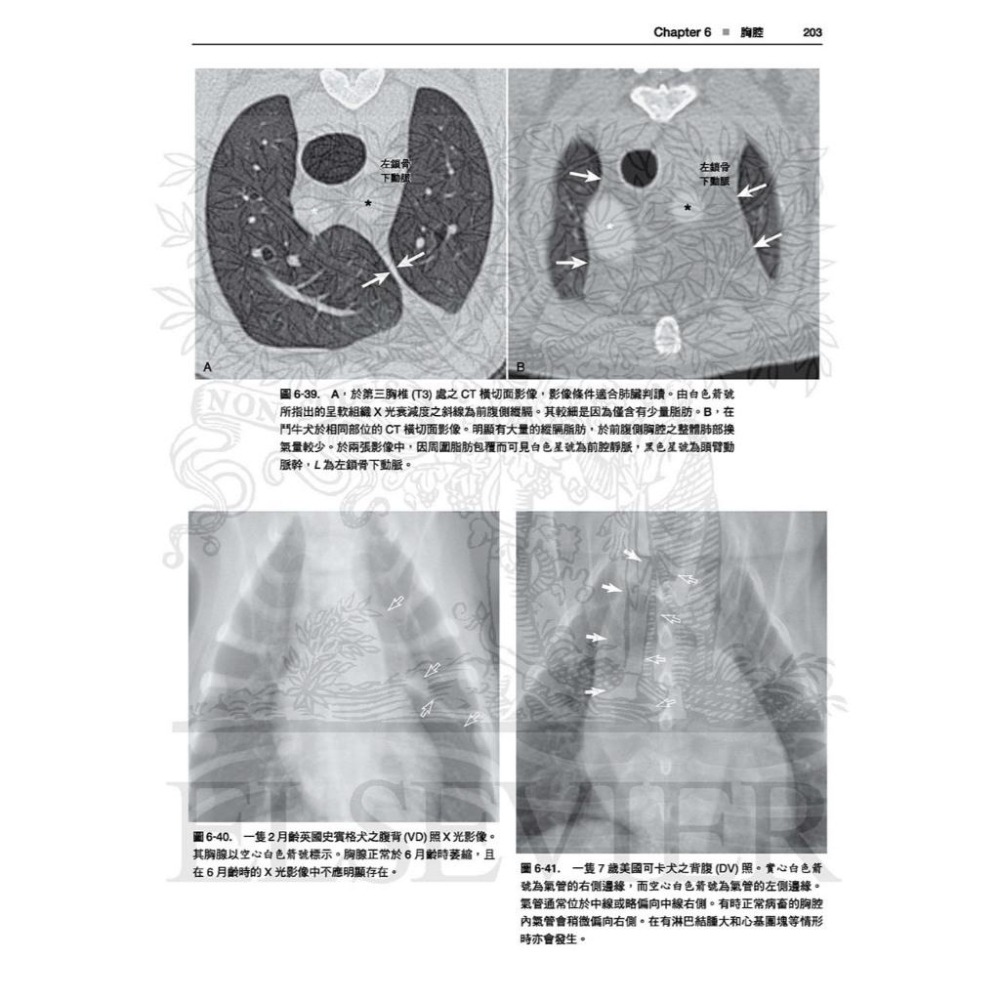

全書皆為高對比的數位影像,除提供正常影像的深入判讀外,亦提供常見且易被誤判為疾病的正常變異;另外並提供多張電腦斷層影像以強調某些結構之影像在放射線學下顯得如此獨特的原因。

最新!更多的電腦斷層影像,詳細解釋某些結構形成獨特放射線學影像的原因。